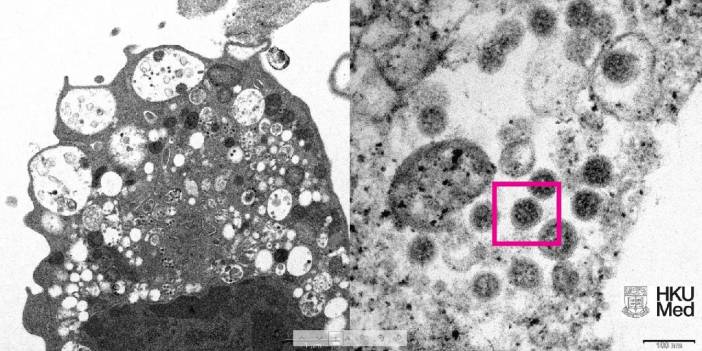

Omicron'un elektron mikroskobu görüntüsü yayınlandı